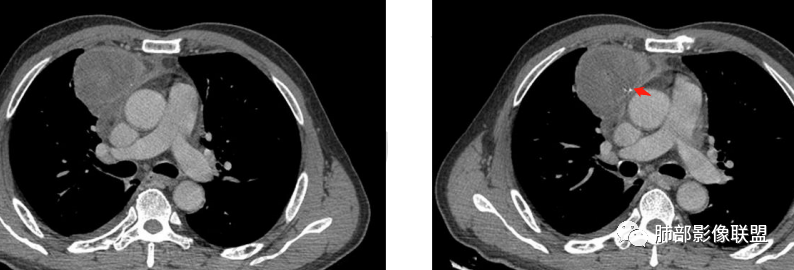

结果:符合B型胸腺瘤伴出血,坏死囊性变,局部脓肿形成

2.胸膜掀起,右侧内乳动脉略增粗,定位右前上纵隔内占位。

3.右上纵隔囊实性占位,边界清楚。中央见点状脂肪密度影,边缘见一点状钙化影,增强不均匀环形强化。

4.四天内病灶变化快,块影增大且不规则,包膜似不完整,边界不清,上份可见浸润或渗出,与周围心脏大血管及心包等间隙不清。胸水增多。

第一次的检查符合胸腺瘤影像学改变,短期内的形态学改变及突然出现的边界模糊或浸润等,符合出血或炎症。